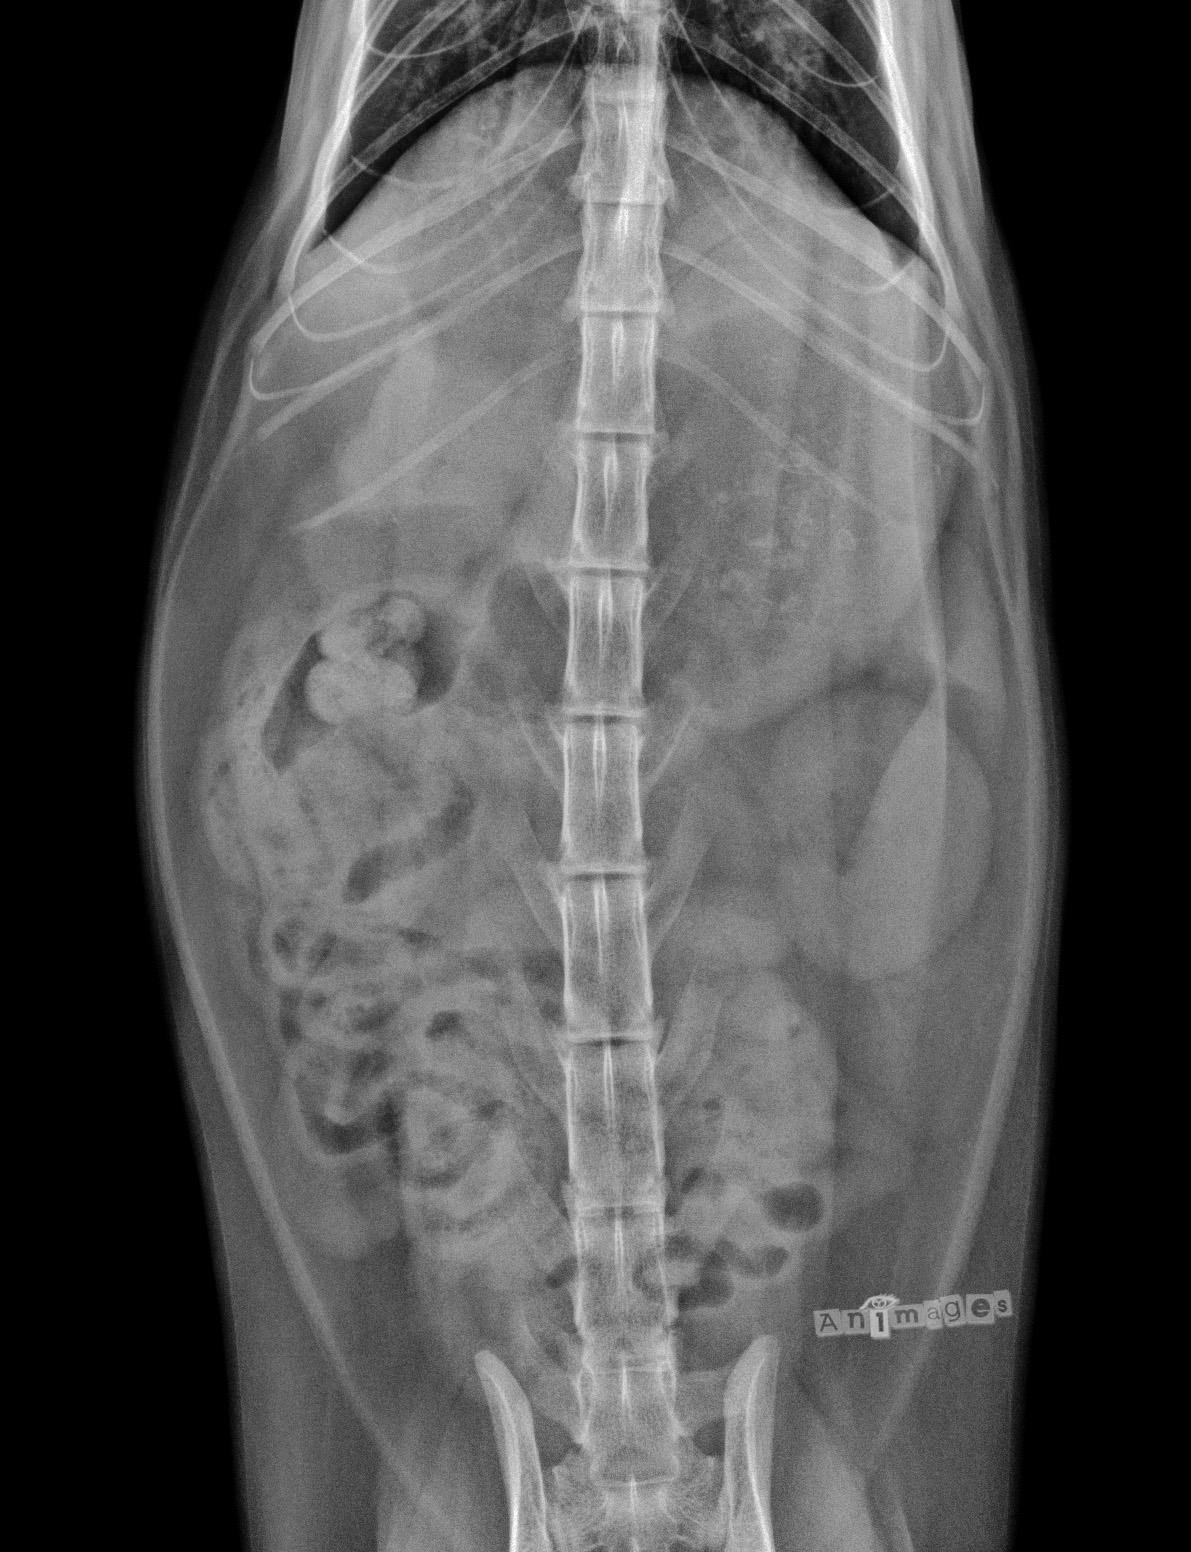

Ventrodorsale